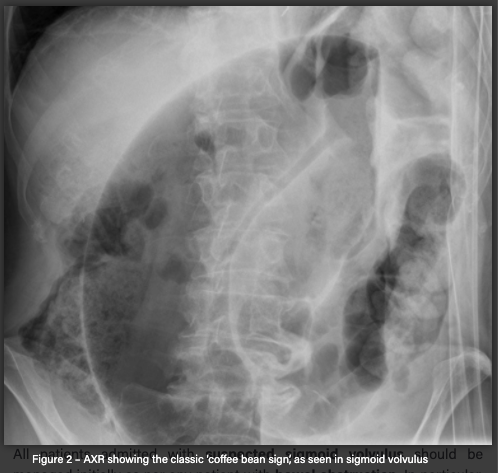

Some places do AXR.

AXR findings

Coffee-bean sign from left iliac fossa

If the ileocaecal valve is incompetent it can also show signs of small bowel dilation